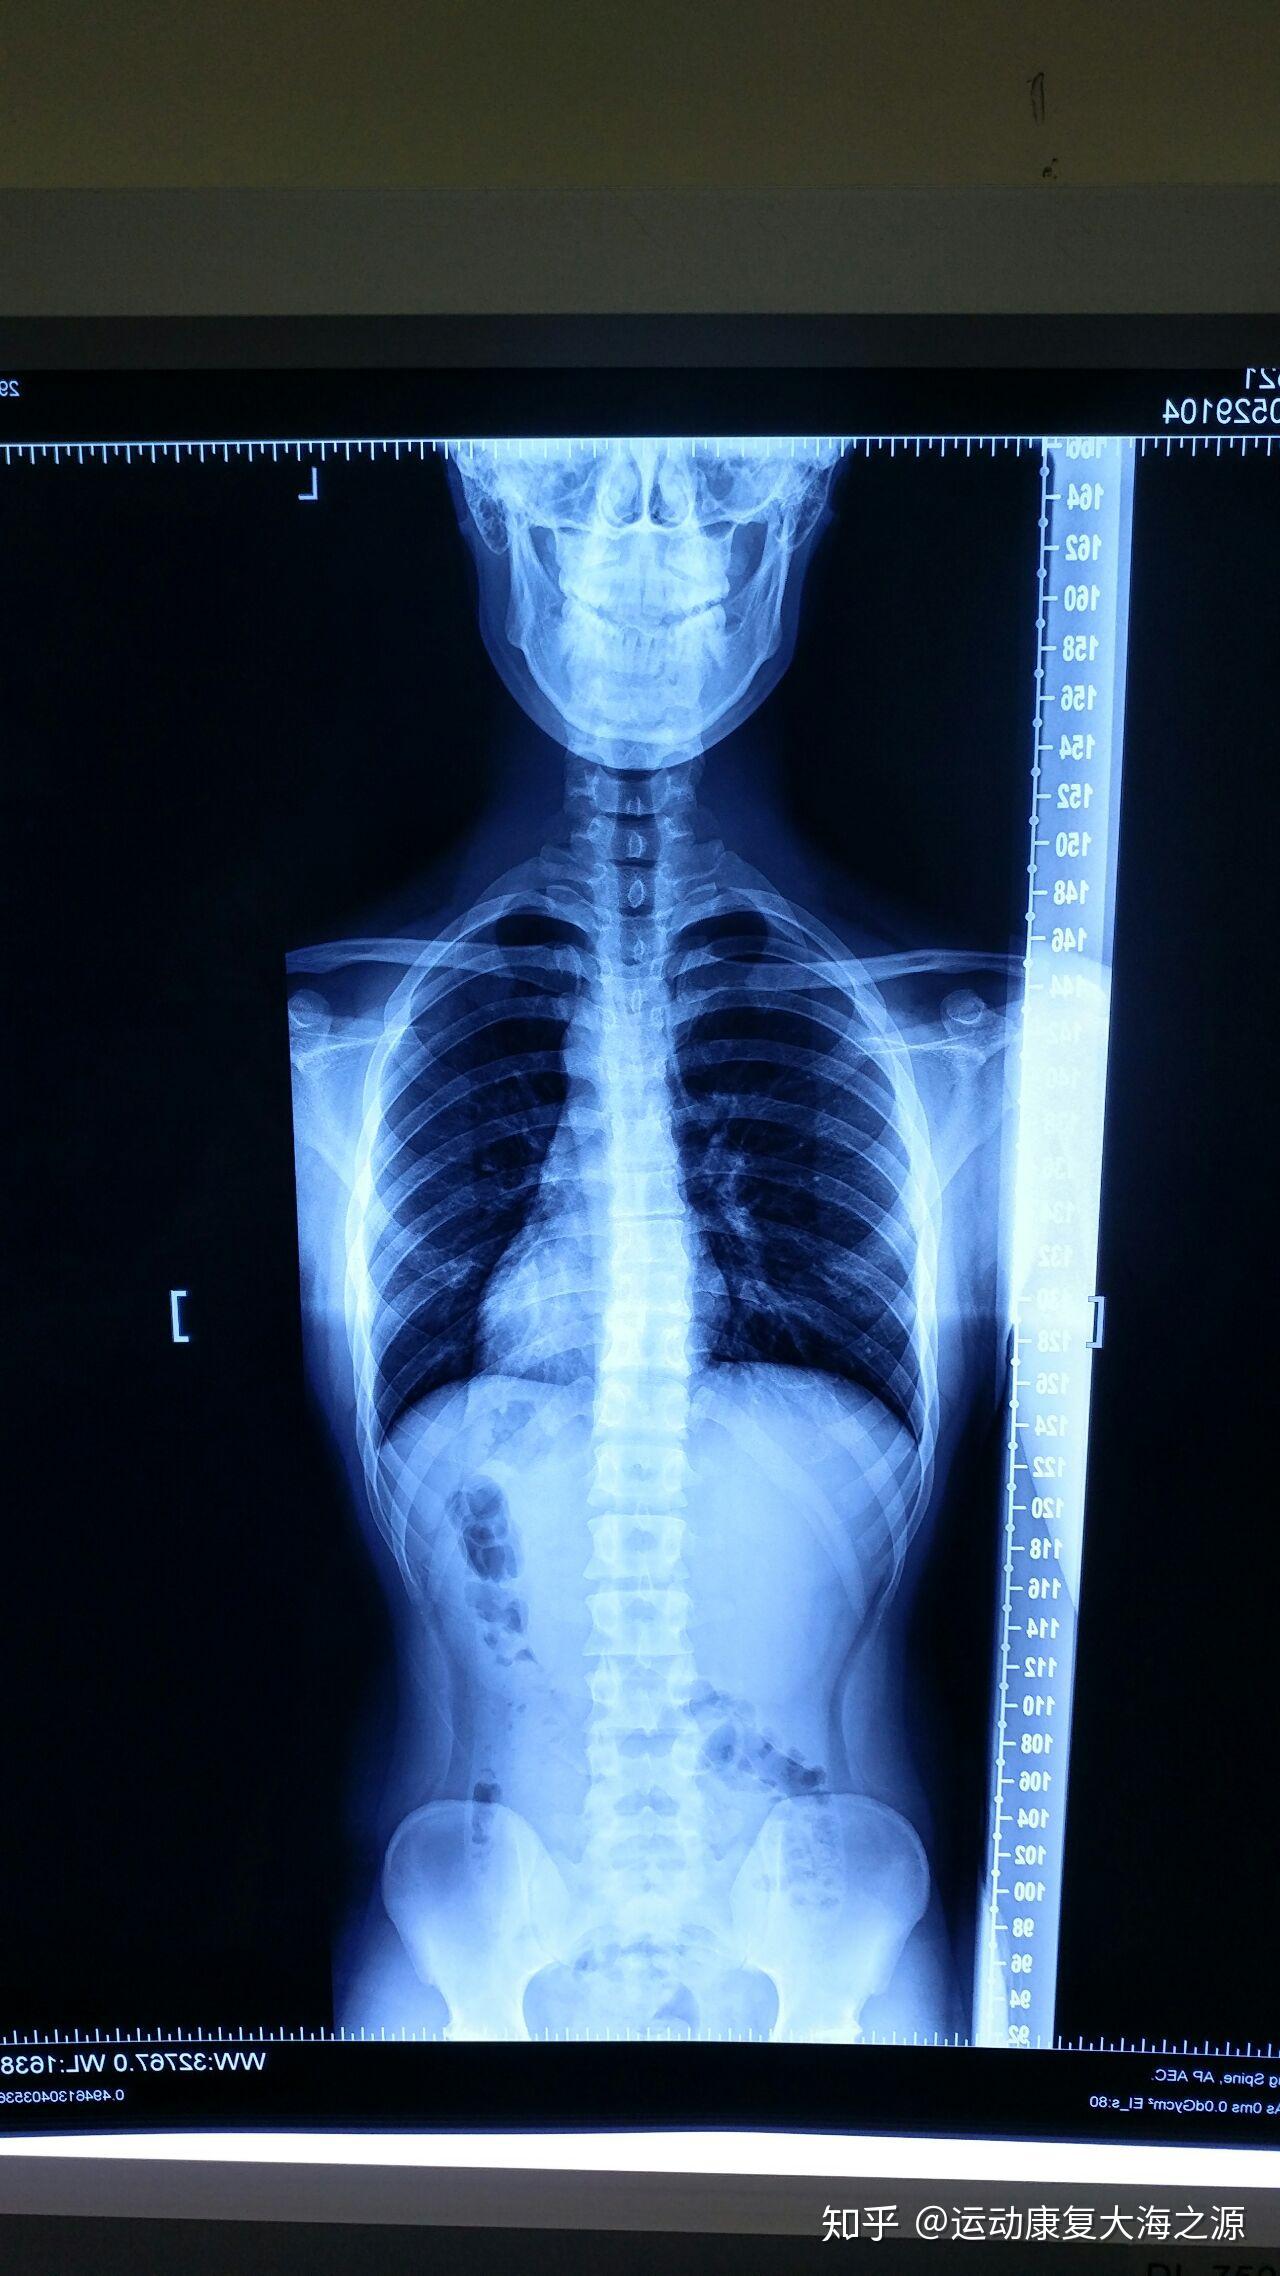

后路手术矫形治疗青少年特发性脊柱侧凸畸形(附图片资料) - 好大夫

图片尺寸1704x2272